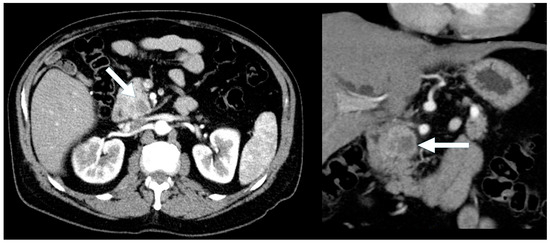

A total of 77 PNEN cases were identified over the study period, of which 39 met the inclusion criteria (Table 1). Cross-sectional imaging was available for all included cases, with CT being the initial modality in 90% and MRI in 10%. Additional imaging with 68Ga-DOTATATE PET or FDG-PET was performed in 82% of cases. Typical PNENs accounted for 54% of the cohort and were characterized by well-defined, hypervascular solid lesions (Figure 1, Figure 2 and Figure 3). In contrast, atypical PNENs comprised 46% (n = 18), including 7 cystic lesions (18%) and 11 hypoenhancing lesions (28%).

Figure 1. A 77-year-old male with an incidental pancreatic mass detected (arrow) on a trauma CT scan. Contrast-enhanced CT images show a 1.7 cm arterially hyperdense lesion in the tail of the pancreas (left, arterial phase). The lesion remains hyperdense relative to the background pancreas on the portal venous phase (right).

Most cases of hypoenhancing PNENs (n = 11) presented symptomatically (64%), and the lesions were significantly larger (median size 4.8 cm vs. 1.7 cm for typical PNENs). Calcifications were observed in 9% of hypoenhancing PNENs. As pointed out, these tumors were significantly more likely to present with advanced disease compared to other PNEN subtypes (Fisher’s exact test, p = 0.016) (Figure 6 and Figure 7).

Figure 6. A 47-year-old male presenting with biliary obstruction. CT (left): Arterial phase imaging shows a 2.5 cm hypodense mass in the pancreatic head (arrow). PET-CT (right): Performed after ERCP and biliary stent placement, demonstrating an intensely FDG-avid pancreatic head mass (arrow), consistent with a poorly differentiated primary neuroendocrine tumor. Metastatic disease involving porta hepatis and peripancreatic lymph nodes, as well as liver metastases, is also evident on the PET.